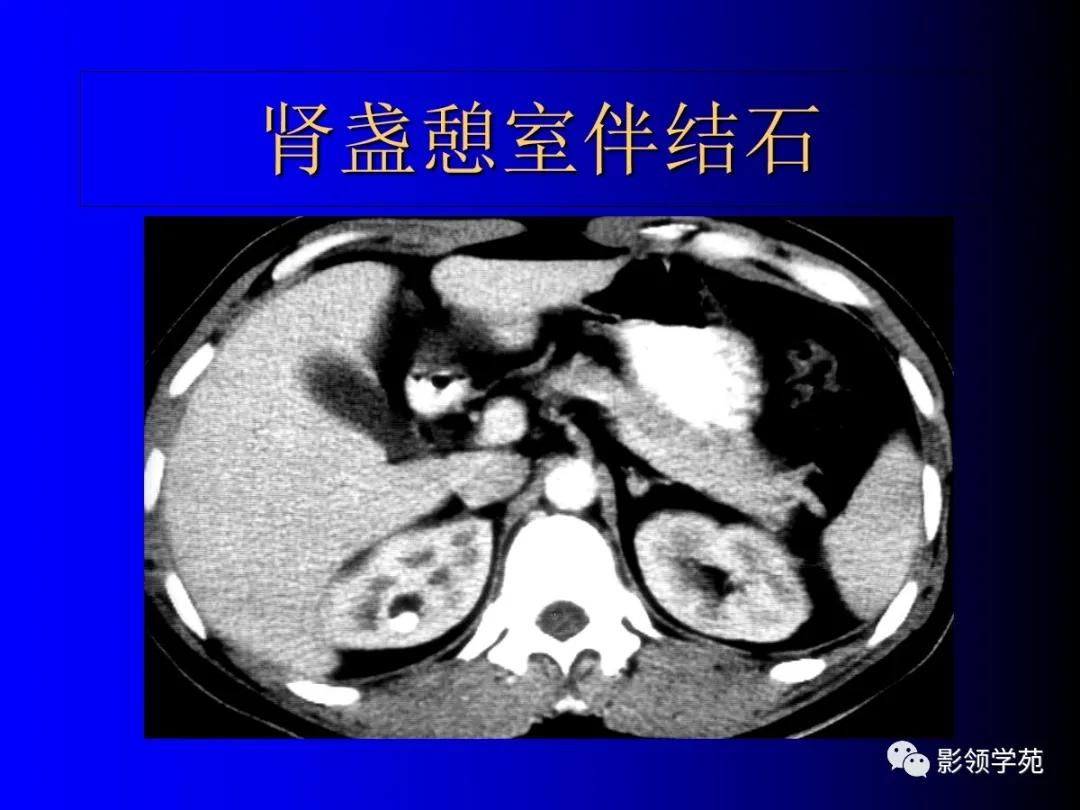

3、肾盂源性囊肿(肾盏憩室)

肾内囊性占位,和肾盂肾盏相通。

-

增强后造影剂进入囊肿。

囊肿内结石发病率高。

肾盂源性囊肿较大,偏中央。

肾盏憩室较小,偏周围。